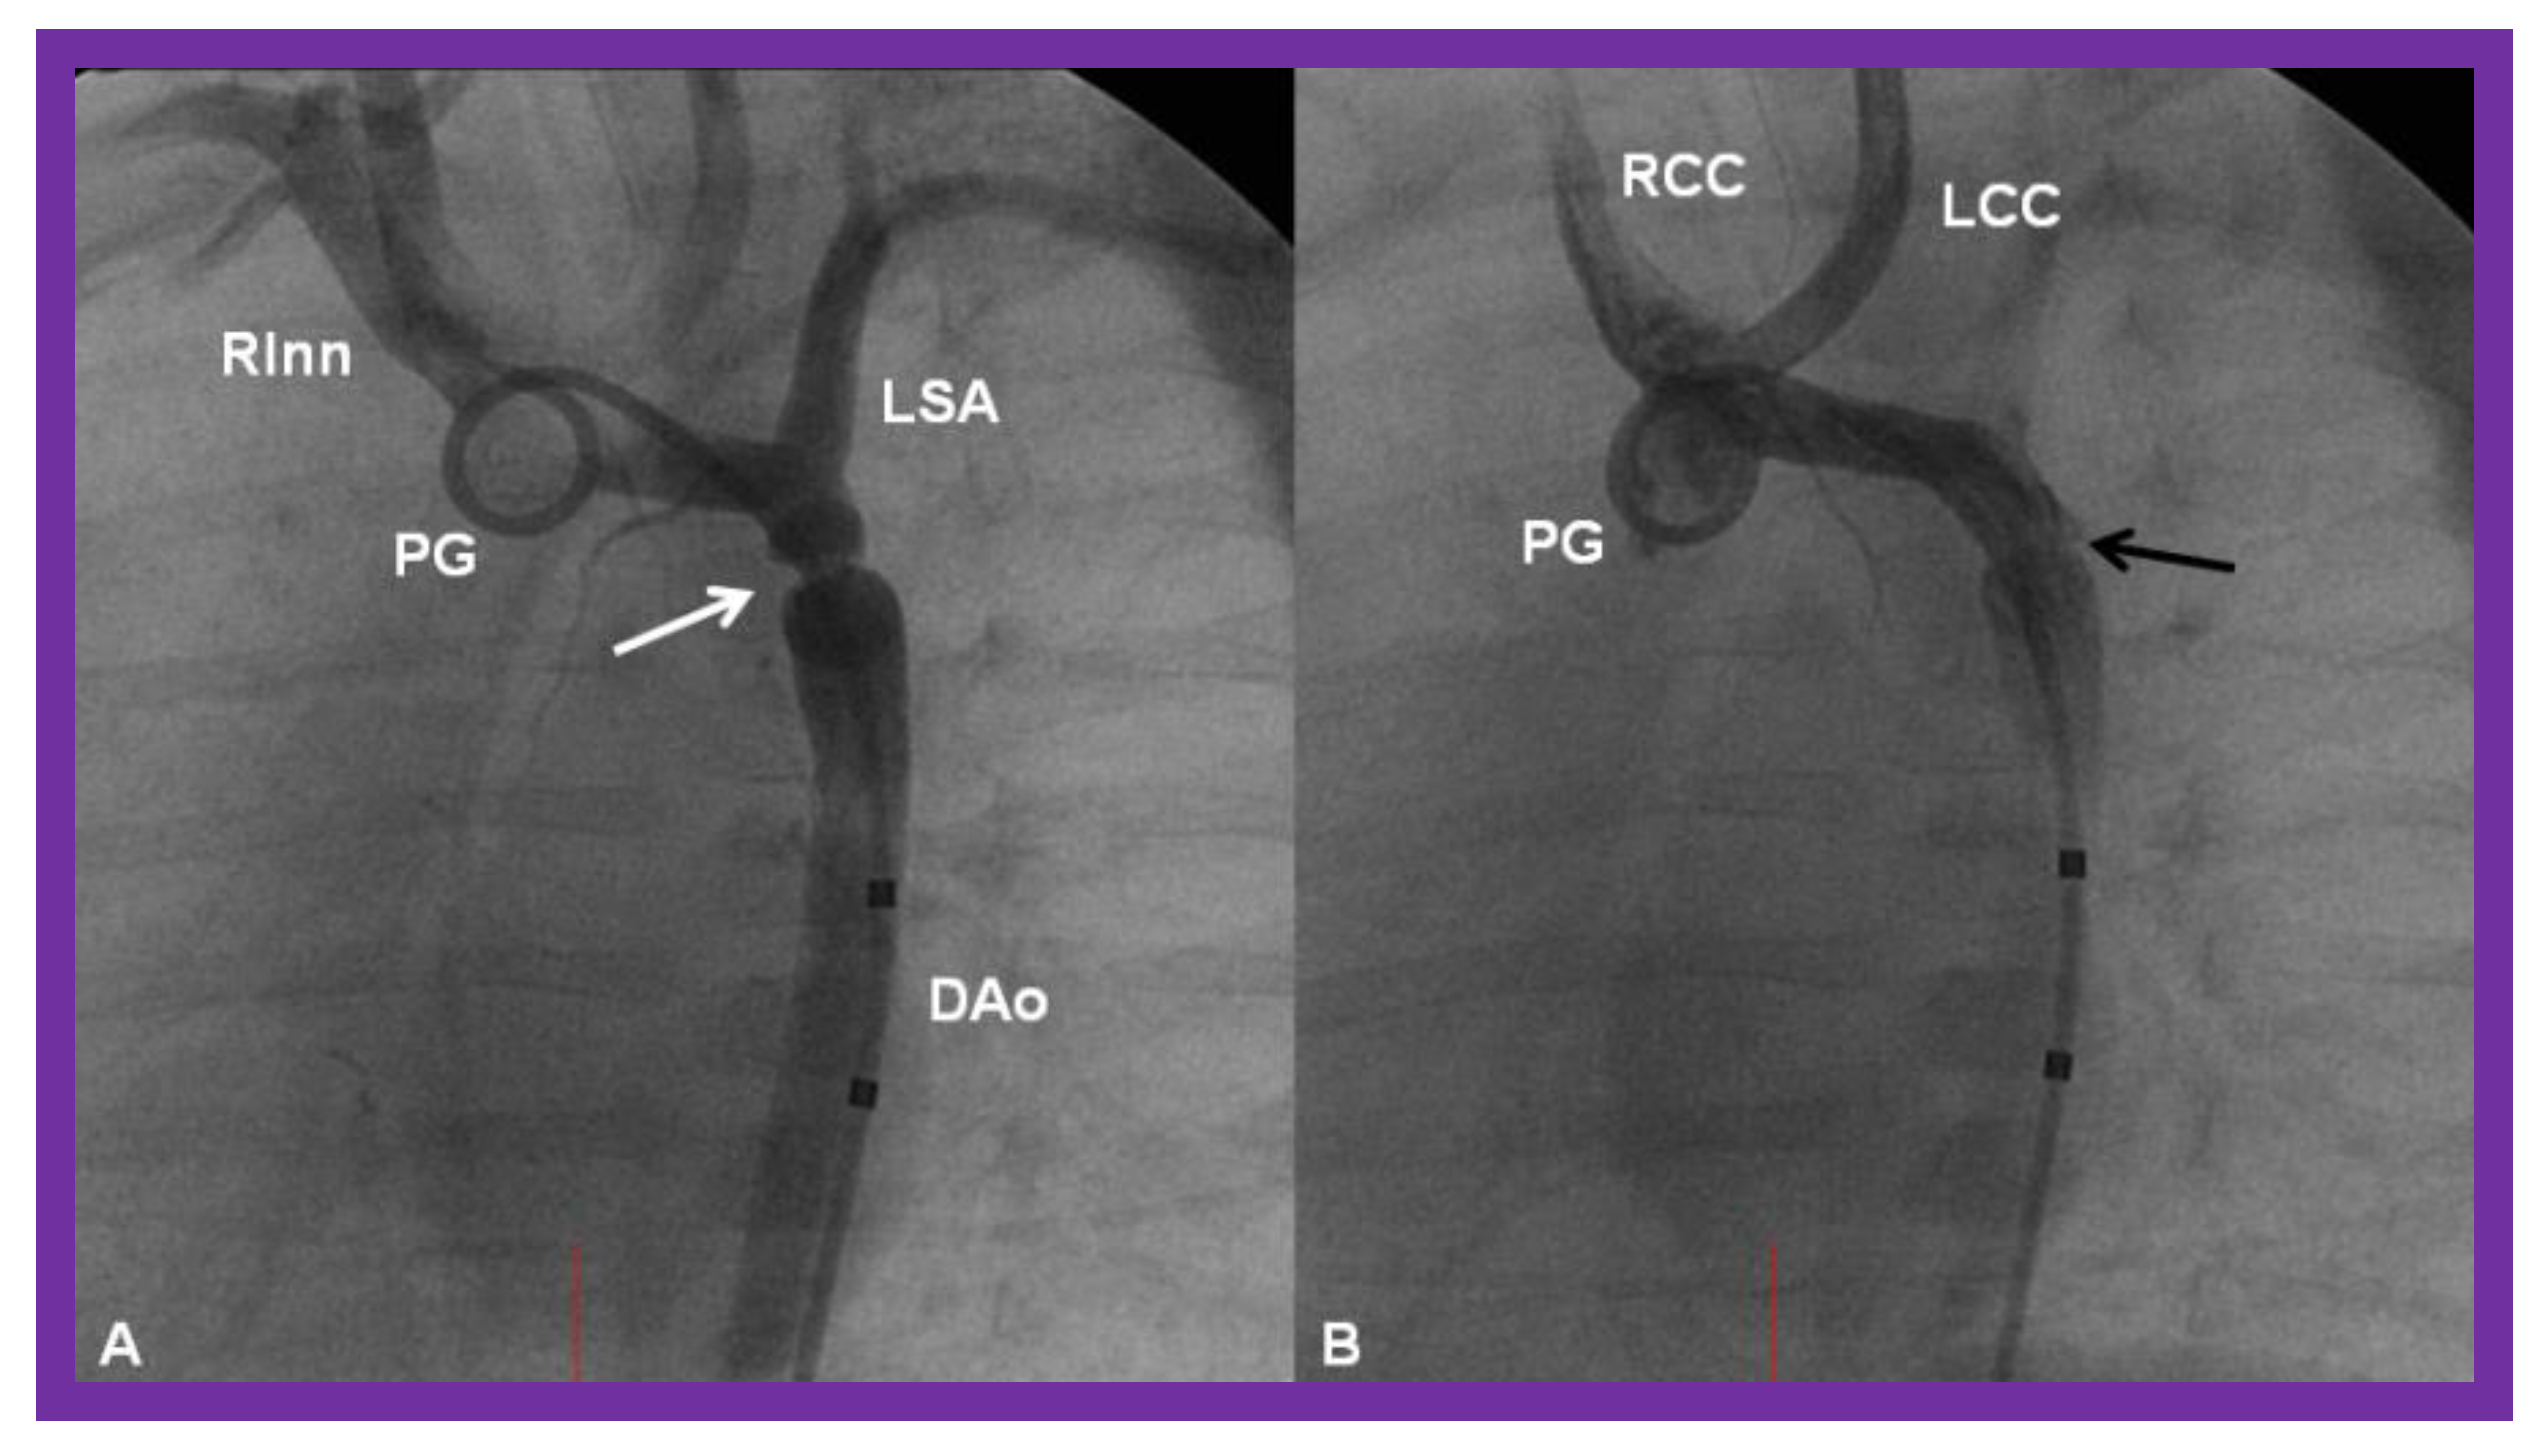

Figure 22.

Bar graph illustrating the fall (p < 0.001) of the peak-to peak systolic pressure gradients (in mmHg) across the aortic coarctation following balloon angioplasty. The reduction in the gradients was seen for all the infant group (left panel) and for all the three subgroups: Balloon angioplasty via trans-umbilical arterial (UA), trans-femoral arterial (FA), and trans-femoral venous anterograde (FVA) routes. The mean and standard deviation (SD) are marked. N represents the number of subjects in each group. Modified from Reference [70].

Figure 23.

Cineangiographic frames from aortic arch angiograms in a 20° left anterior oblique views, illustrating a narrowed (coarcted) aortic segment (arrow) priot to balloon angioplasty (A) which improved following balloon angioplasty (B). Note mild hypoplasia of the distal transverse aortic arch and isthmus. AAo, ascending aorta; DAo, descending aorta; LCC, left common carotid artery; LSA, left subclavian artery; NG, nasogastric tube; PG, pigtail catheter; RInn. right innominate artery. Modified from Reference [90].

Figure 24.

Cineangiographic frames from aortic arch angiograms in 20° left anterior oblique projection, illustrating a coarcted aortic segment (white arrow) prior to balloon angioplasty (A) which widened (black arrow) following balloon angioplasty (B) in a neonate who had had the Norwood procedure earlier. DAo, descending aorta; LCC, left common carotid artery; LSA, left subclavian artery; PG, pigtail catheter; RCC, right common carotid artery; RInn, right innominate artery. Reproduced from Reference [58].